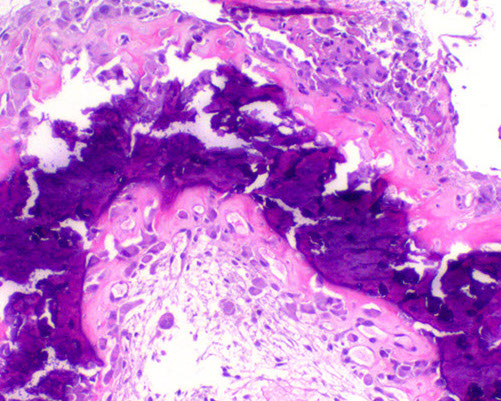

Hyperparathyroidism - Brown tumors. Right image shows zone of bone resorption in center c defect filled c fibroblastic tisuue, and around the periphery is osteoid-producing area that looks like fibrous dysplasia. Image on left is close of area replacing fibroblastic tissue c lots of osteoclast-like GCs, that may lead to misdiagnosis of giant cell tumor (except GC tumors usually lack fibrogenic stroma)

Brown Tumor

Bone loss causes microfractures and hemorrhage causing macrophage influx and reparative fibrous tissue

Brown from vascularity, hemorrhage and hemosiderin deposition

"Brown tumors" of bone are caused by hemorrhage and hyperparathyroidism

- may also be caused by pseudohyperparathyroidism, but is usually due to parathyroid adenoma, hyperplasia, or rarely carcinoma or chronic renal failure

Micro: Osteoclasts line cystic spaces (tunneling), which also have a very fibrous stroma, inc formation of woven bone, and peritrabecular fibrosis, MNGCs